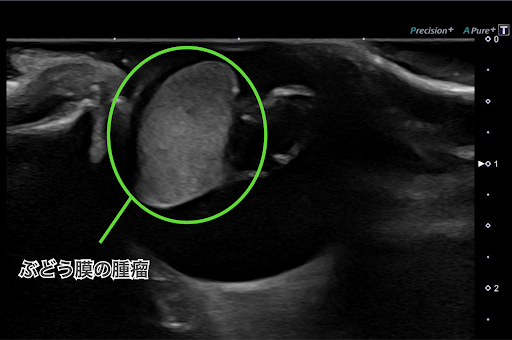

スリットランプ検査と眼部エコー検査を行ったところ、左眼の内眼角側の毛様体領域に腫瘤状病変が確認されました。

こちらが眼部エコー検査の画像です。

眼内の内側の白い部分が腫瘤です。